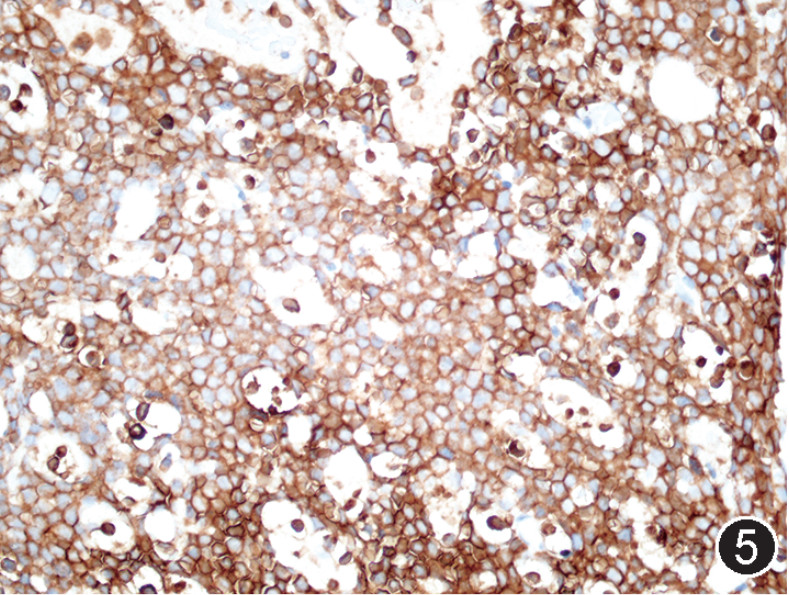

图注:图1 骨髓涂片中的肿瘤细胞(瑞氏染色,×1 000);图2 骨髓活检中的肿瘤细胞(HE, 高倍放大);图3 免疫组织化学染色,CD20部分阳性(EnVision法,中倍放大);图4 免疫组织化学染色,CD19阳性;图5 免疫组织化学染色,CD10阳性;图 6 免疫组织化学染色,MYC阳性,图 7 免疫组织化学染色,bcl-2阴性;图 8 免疫组织化学染色,Ki-67阳性指数约 80%。

根据以上检查结果,需要考虑的淋巴瘤类型包括BL、HGBL、原始细胞标记阴性B-ALL(占B-ALL<5%)以及罕见CD5-CD10+MCL的母细胞变型,须进一步进行免疫组化(包括CyclinD1、CD10、BCL6、MUM1、MYC、BCL2、Ki67)、染色体核型、FISH检测(MYC、BCL2、BCL6、IgH-CCND1)以及白血病融合基因检测加以区分。最终流式细胞学示肿瘤细胞CD38强表达、表达sIgM、sIgD和胞膜Kappa,免疫组化CyclinD1-,细胞遗传学示复杂核型,FISH检测MYC和bcl-6基因重排阳性,白血病52种融合基因阴性,二代测序提示存在TP53、CCND3、MYC、TCF3、FOXO1等HGBL、DLBCL中而非B-ALL/LBL中的常见基因突变类型,因此综合诊断为HGBL伴MYC和bcl-6基因重排。